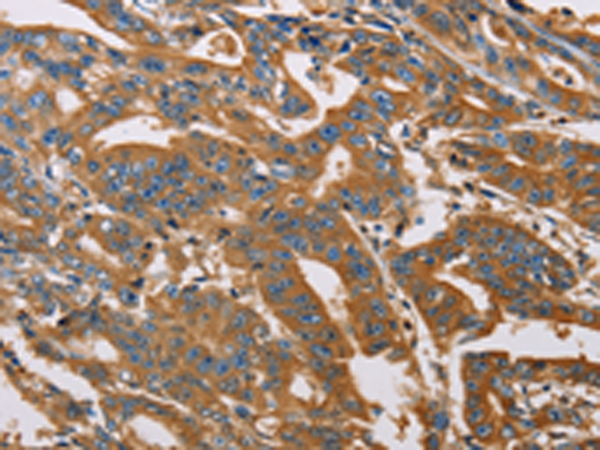

分类: 科研抗体货号: P06989别名: CPP32; SCA-1; CPP32B应用: WB,IHC反应种属: Human, Mouse, Rat

分类: 科研抗体货号: P06971别名: FETA, HPAFP应用: WB,IHC反应种属: Human

分类: 科研抗体货号: P06951别名: MEH; EPHX; EPOX; HYL1应用: IHC反应种属: Human, Mouse, Rat

分类: 科研抗体货号: P06988别名: BCL2L4应用: WB,IHC反应种属: Human, Mouse, Rat

分类: 科研抗体货号: P06970别名: ADDA应用: IHC反应种属: Human, Mouse, Rat

分类: 科研抗体货号: P06950别名: ATLD2应用: WB,IHC反应种属: Human, Mouse, Rat

分类: 科研抗体货号: P06987别名: BBC2; BCL2L8应用: IHC反应种属: Human

分类: 科研抗体货号: P06969别名: GCS1L; CENTA1; p42IP4应用: WB,IHC反应种属: Human, Mouse

分类: 科研抗体货号: P06949别名: 1A; GDIL; MRX41; MRX48; OPHN2; XAP-4; RABGD1A; RABGDIA应用: WB,IHC反应种属: Human, Mouse, Rat

分类: 科研抗体货号: P06986别名:应用: IHC反应种属: Human